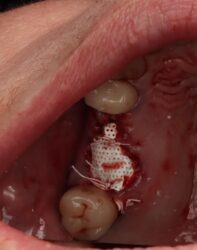

jorbrown posted an update a year ago

Case here for a maxillary partial overdenture. How do these positions look prosthetically in respect to their existing partial? I placed them as best I could. Also how far subcrestal should I am for? 1-2mm?